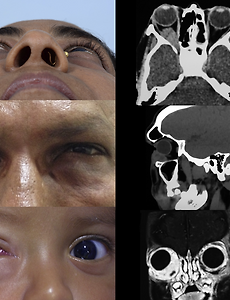

아스퍼질러스증, 안와의 아스페르길루스증, Orbial Aspergillosis 의 진단과 치료 아스퍼질러스(Aspergillosis)는 면역기능이 저하되지 않은 정상인에서는 드물게, 면역저하자에서는 다소 흔하게 발견되는 곰팡이, 진균입니다. 안와 아스퍼질러스증(Orbital aspergillosis)은 비교적 드문 질환이나 최근들어 항생제, 스테로이드제, 항암제의 빈번한 사용으로 인하여 점차 증가하는 추세를 보이고 있습니다. 주로 부비동에서 감염이 파급되어 발생하며 심한 경우 안와나 두개강 내까지 전파되기도 하며 항암제 사용이나 후천성면역결핍증 등으로 인해 저항력이 감퇴된 환자에서 주로 발생합니다. 진단은 임상양상이나 단순 방사선 소견에만 의존할 수 없고 조직생검을 하여 병리조직학적 검사를 반드시 시행해야 합니다. 격벽과 분지된 균사가 약 45° 각도로 배열되어 형성된 균사가 발견되어야 하는데, .. 2018. 8. 24.

Aspergillus, 아스퍼질러스, 국균에 의한 눈주위 감염, 안와 감염, Orbital Aspergillosis 아스퍼길러스, 아스퍼질러스 아스페르길루스, 아스페르질루스 혹은 국균증이라고 불리는, Aspergillosis는, 칸디다균(Candida spp.)에 이어 면역기능이 저하된 환자에게서 두 번째로 흔하게 발생하는 기회감염으로 알려져 있습니다. 침윤성 아스퍼질러스증(Invasive aspergillosis)은 주로 코와 부비동에서 시작하게 되는데, 코에만 감염이 머무르지 않고, 주위로 감염이 퍼져나갈수있습니다. 앞서 살펴본, 뮤코르 진균증(털곰팡이증, mucormycosis)에서와 마찬가지로, [안과 질환과 안과 치료/성형안과] - 뮤코르 진균증, 모균증, 뮤코르 곰팡이에 의한 안와 연조직염, Orbital Mucormycosis [안과 질환과 안과 치료/성형안과] - 뮤코르 진균증, rhinocerebral.. 2018. 8. 23.